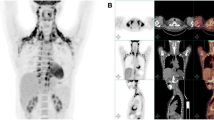

Cypess AM, Lehman S, Williams G, Tal I, Rodman D, Goldfine AB, Kuo FC, Palmer EL, Tseng YH, Doria A et al (2009) Identification and importance of brown adipose tissue in adult humans. N Engl J Med 360:1509–1517

Virtanen KA, Lidell ME, Orava J, Heglind M, Westergren R, Niemi T, Taittonen M, Laine J, Savisto NJ, Enerback S et al (2009) Functional brown adipose tissue in healthy adults. N Engl J Med 360:1518–1525

Marken Lichtenbelt WD, Vanhommerig JW, Smulders NM, Drossaerts JM, Kemerink GJ, Bouvy ND, Schrauwen P, Teule GJ (2009) Cold-activated brown adipose tissue in healthy men. N Engl J Med 360:1500–1508